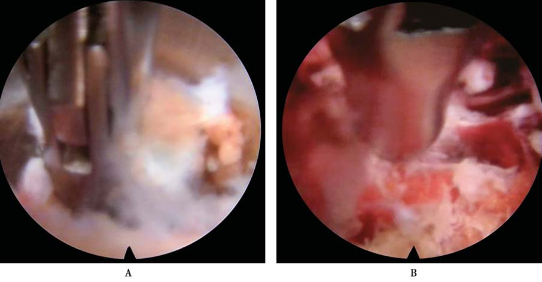

摘除突出髓核组织(图26)。

图26 摘除突出髓核组织

清理髓核组织碎片(图27)。

图27 清理髓核组织碎片

椎体后缘成形(图28)。

图28 L5椎体后缘